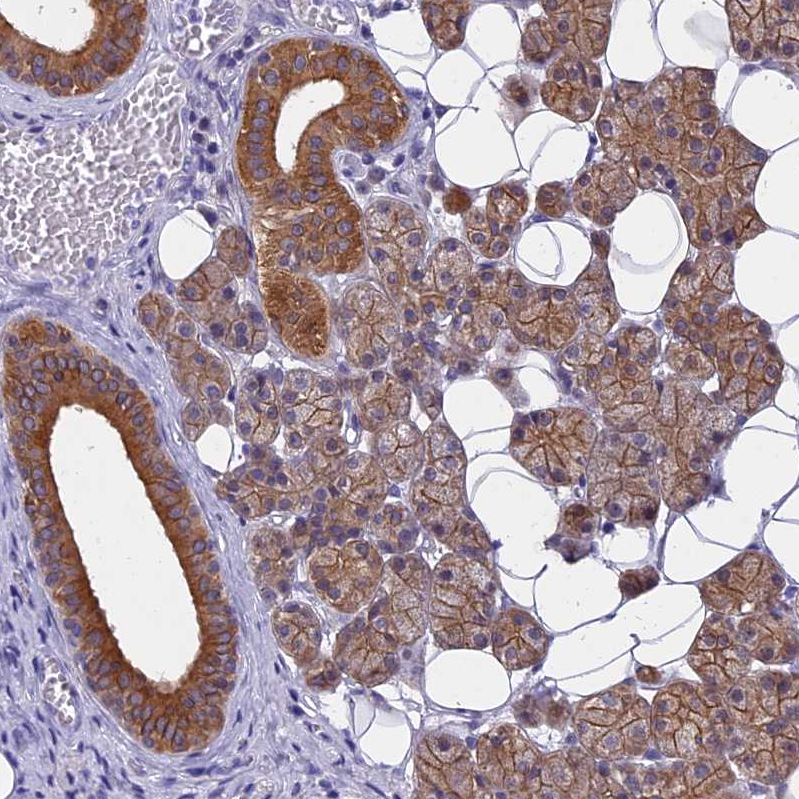

Immunohistochemical staining of human cerebral cortex, kidney, liver and salivary gland using Anti-STUB1 antibody HPA041222 (A) shows similar protein distribution across tissues to independent antibody HPA043531 (B).